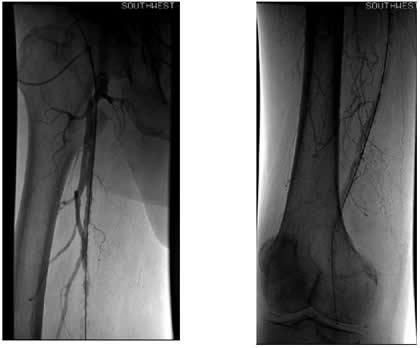

Case 1: An 84-year-old male with rest pain, who had undergone prior revascularization with covered stents, represents with recurrent rest pain. The prior stents had come close to the origin of the SFA and at that time there had been some narrowing. Exposure was provided by performing a cut down and patching the CFA-proximal SFA to the level of the stents, following which gentle thrombectomy was performed, and a wire passed down. The angiogram demonstrated a distal lesion at the adductor canal which contributed to the thrombosis (Figure 1A). The patient underwent a day of lysis, following which cryoablation was used to treat the distal lesion (Figure 1B) and completion angiogram showed restoration of limb perfusion (Figure 1C).

Case 2: A 74-year-old male with new onset severe claudication and threatened toes on the right side. An up-and-over wire was able to be advanced into the superficial femoral artery (but was totally occlusive). Cryoablation restored patency (Figure 2).

![]() |

| Figure 2 |